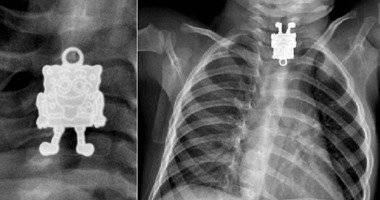

وفقا لموقع فوكس نيوز فإن الأشعة السينية على الصدر لطفل مستشفى جامعة

الملك عبدالعزيز فى جدة بالمملكة العربية السعودية كشفت أن الطفل 16 شهرا قد ابتلع

قلادة أخته والتى على شكل سبونج بوب، ووقفت فى المرئ، ويعانى منها الطفل.

سبونج بوب الذى يبتسم مخرجا لسانه بتفاصيله الكاملة داخل الأشعة.